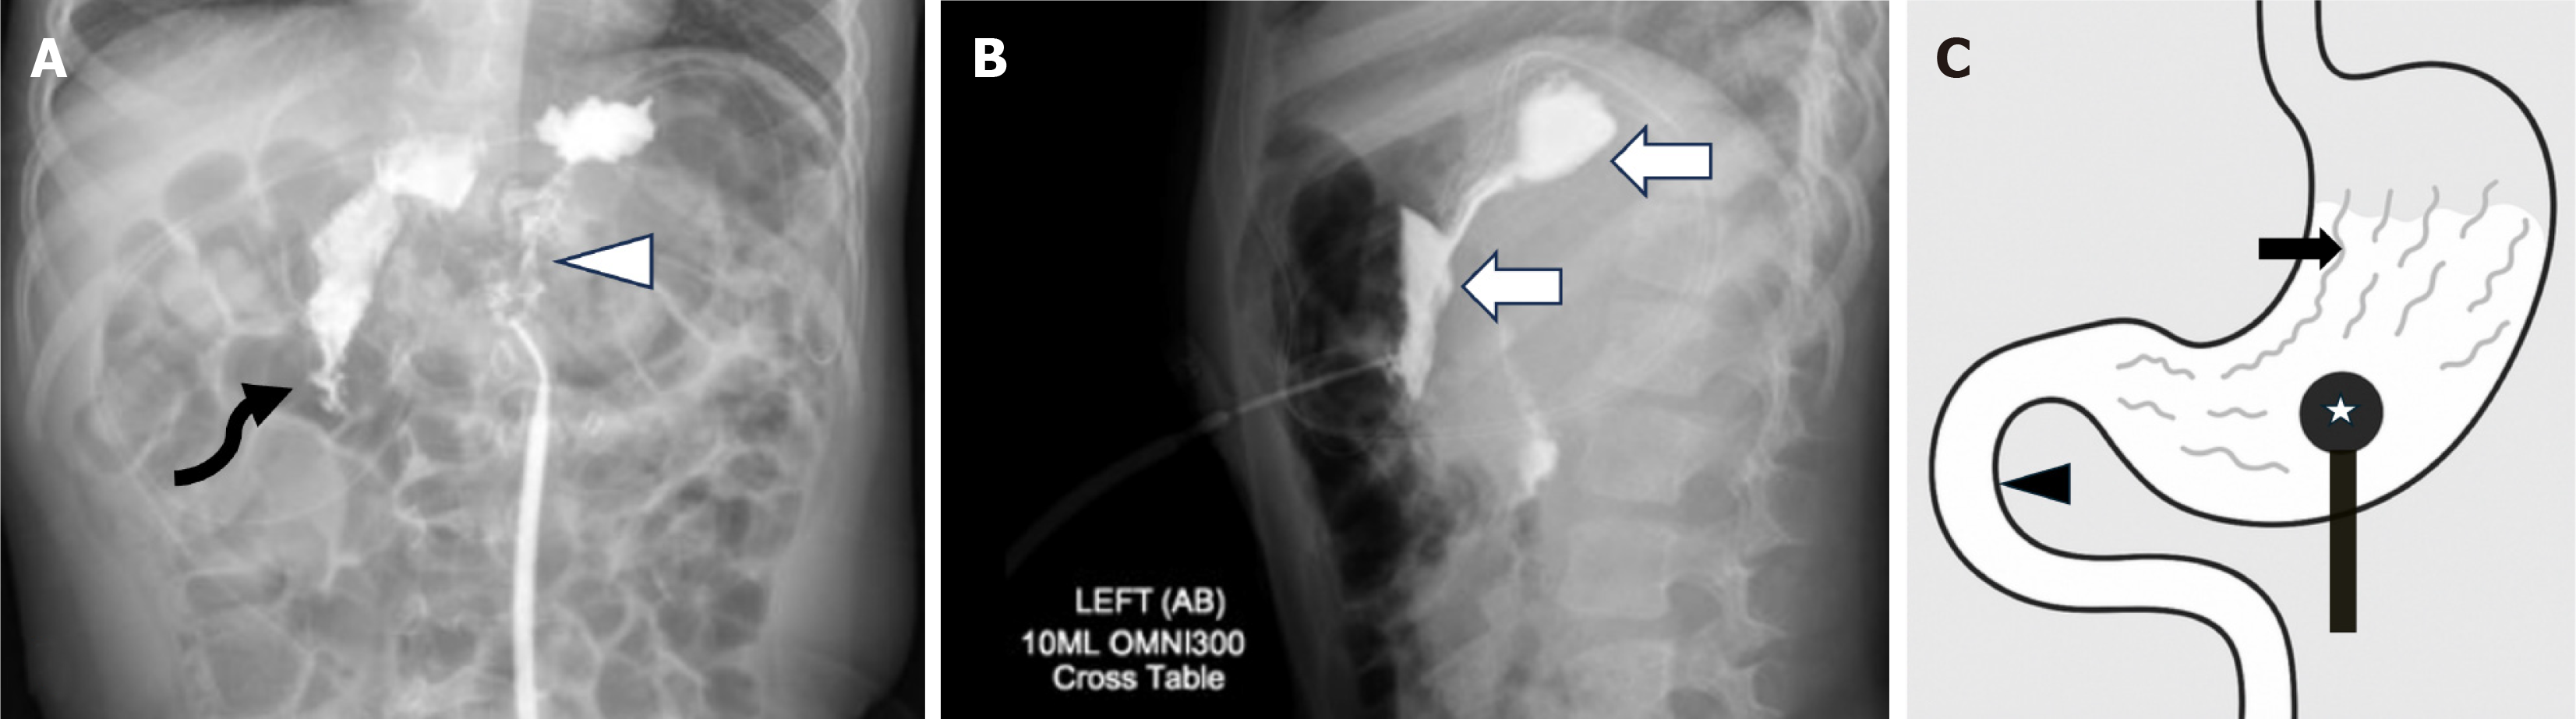

Figure 2 Normal contrast abdominal radiography study for gastrostomy tube.

A: Frontal; B: Cross table lateral post-injection radiographs show normal outlining of the gastric contour ( white arrows) and rugal folds (arrowheads). There is normal drainage of contrast into the duodenum (curved arrow). No extraluminal spillage noted; C: It is a schematic diagram depicting normal findings which should be looked at including filling defects of gastric rugae in the contrast pool (black arrow), more importantly the filling defect of the gastrostomy tube ballon, gastric contour and tracking of contrast into the duodenum (black arrowhead).